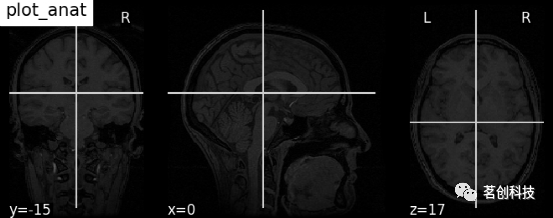

plot_anat:用函数plot_anat绘制解剖图像。如可视化haxby数据集解剖图像。

plotting.plot_anat(haxby_anat_filename, title="plot_anat")